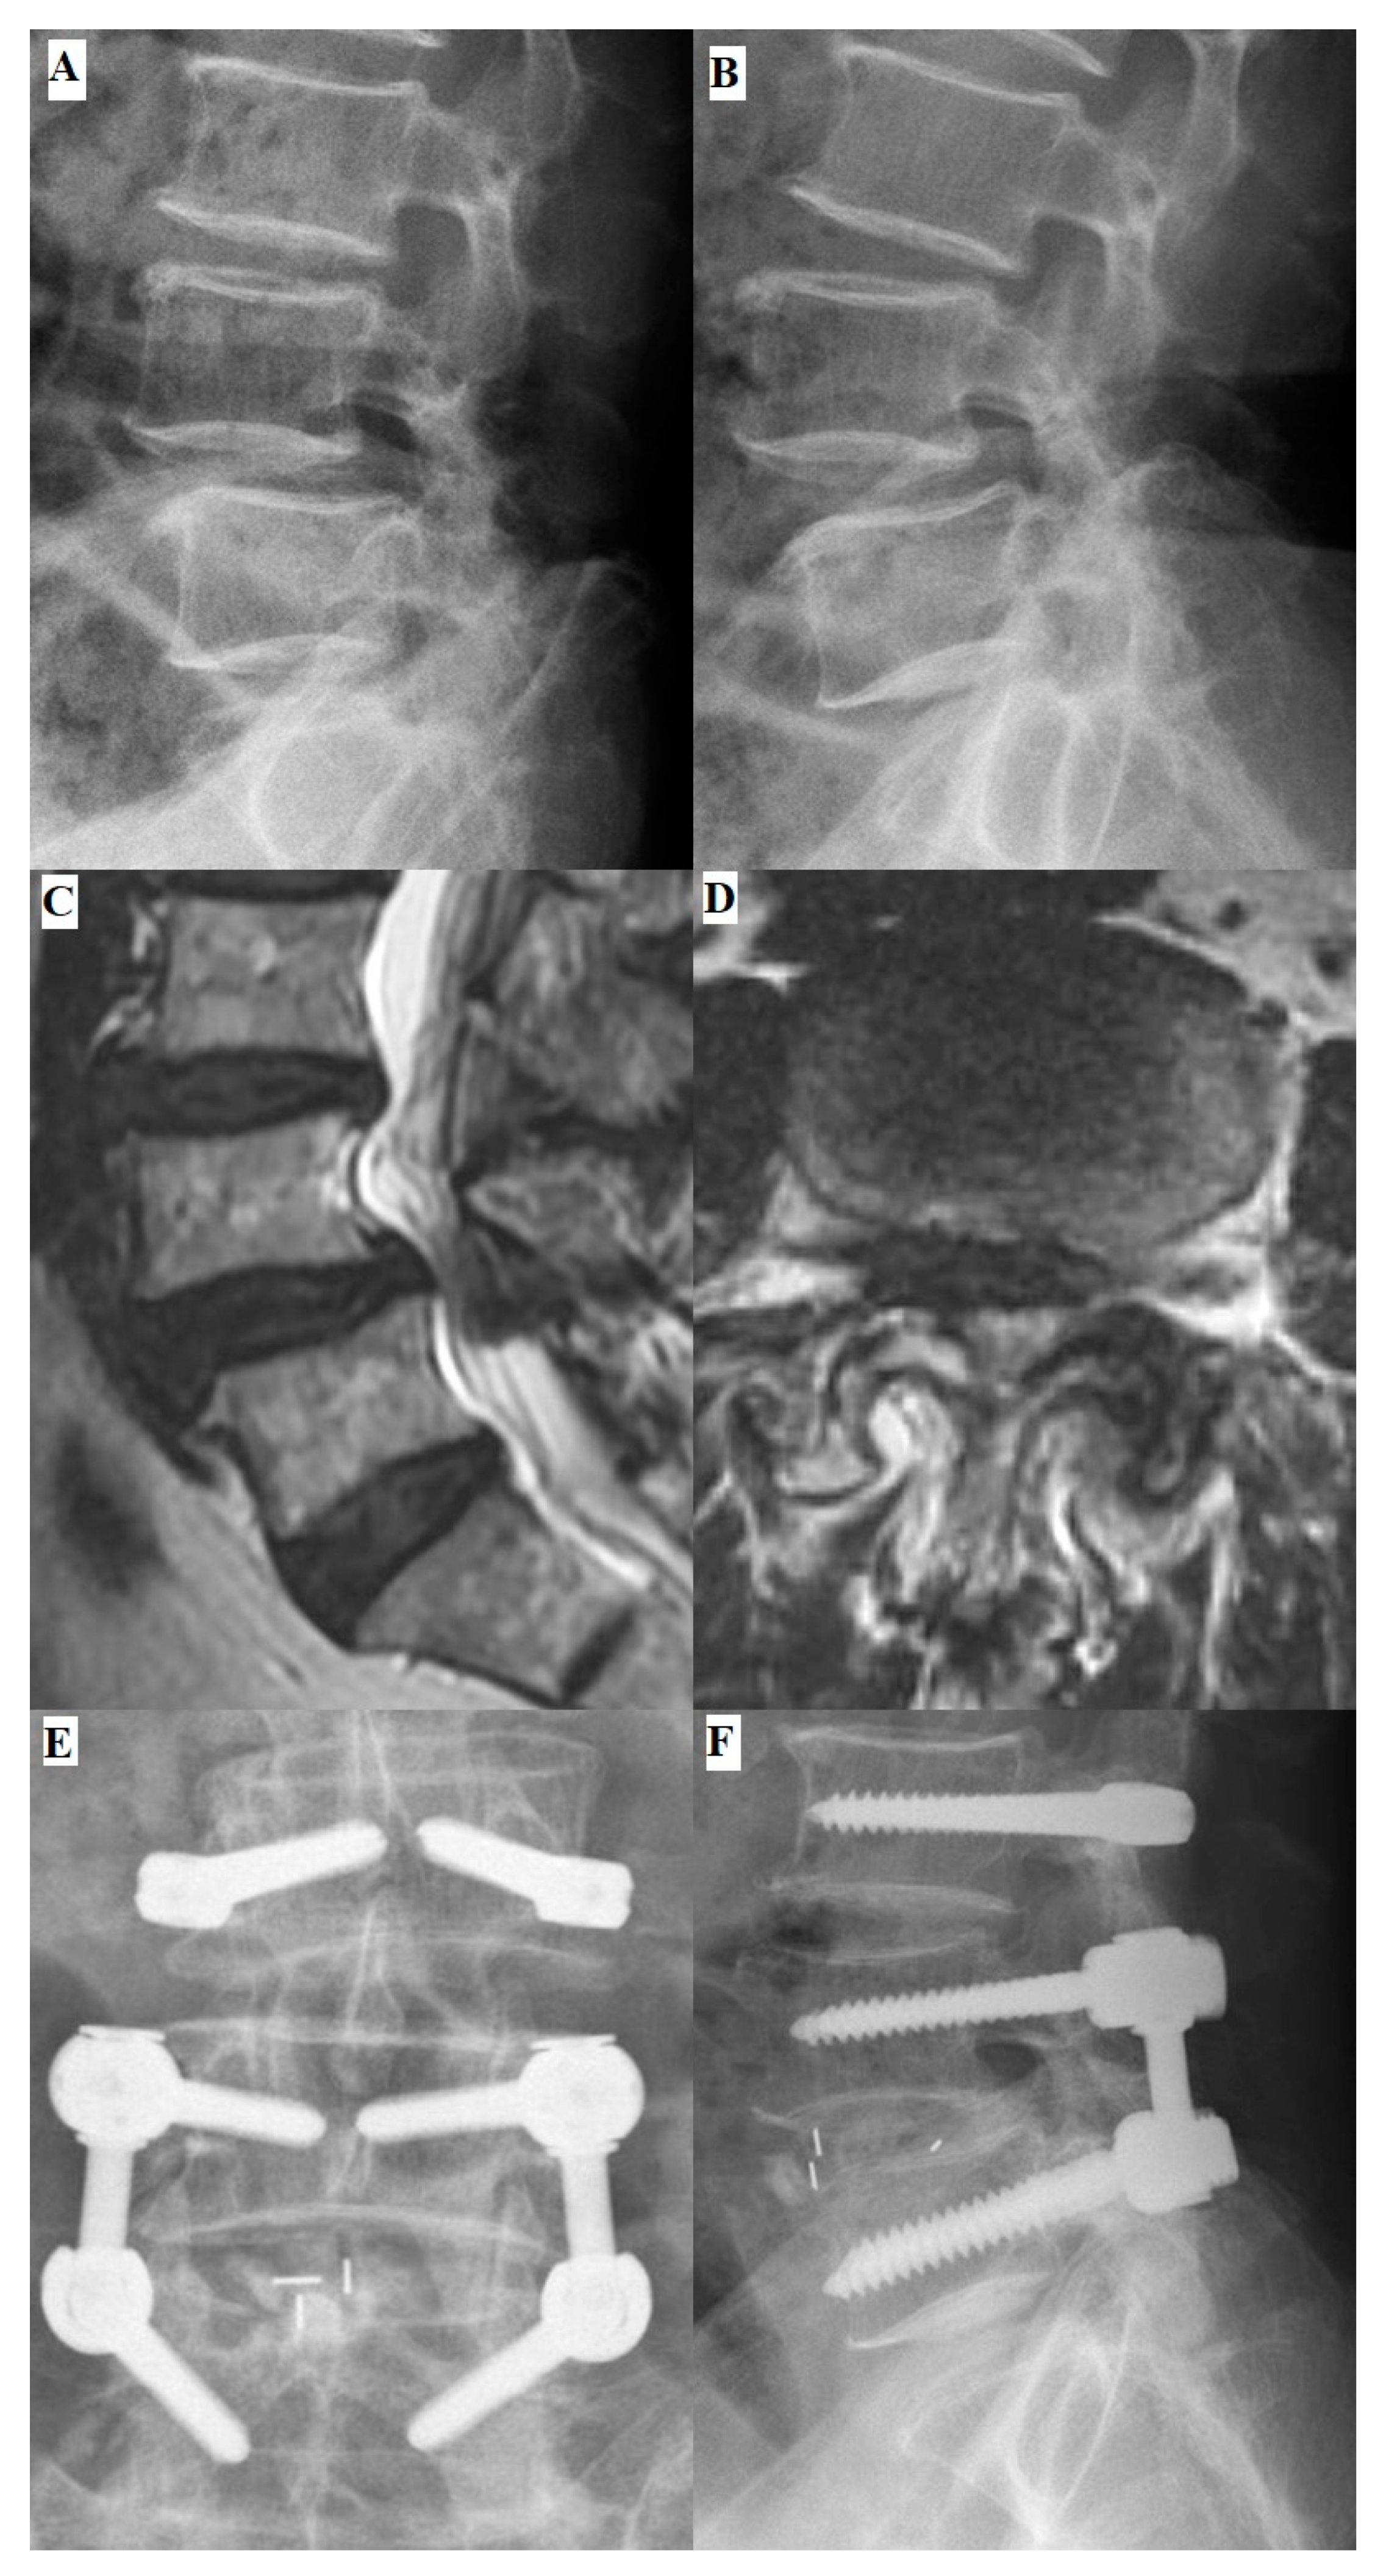

2.3. Surgical Techniques